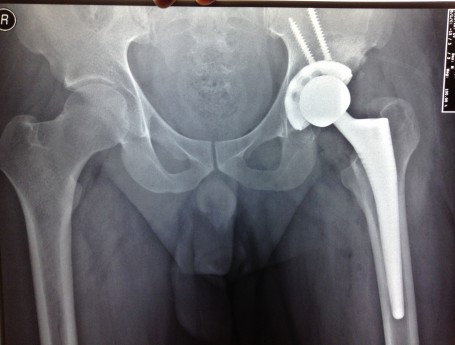

high hip dislocation

• high hip dislocation